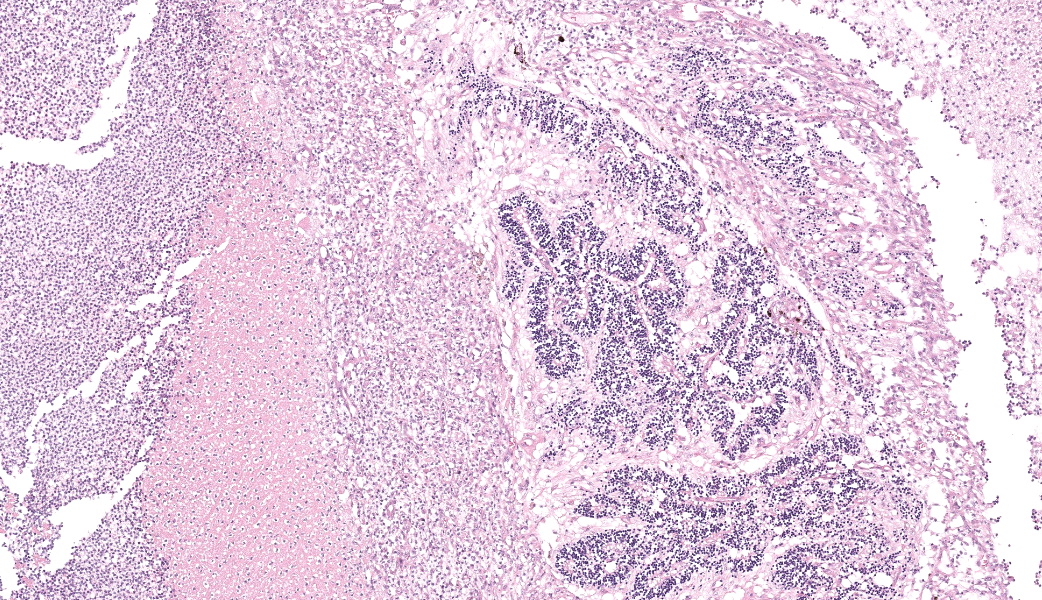

Filling all ocular chambers and coating the surfaces of intraocular structures are vast accumulations of exudate consisting of myriad degenerate and intact neutrophils, many macrophages, abundant amounts of fibrinous to proteinic material, abundant necrotic cellular debris, occasional pools of extravasated erythrocytes, and multifocal colonies of mixed bacteria (rods and coccobacilli). Centrally incorporated into the inflammatory exudates is a ruptured lens which lacks a capsule in many areas and has highly undulating free capsule margins regionally. The lenticular stroma is variably vacuolated with the following features: streaks of pallor, Morgagnian globules, many infiltrating leukocytes (mostly neutrophils), and occasional pockets of similar bacteria. The retina is diffusely detached and largely inapparent apart from remnant segments of atrophied and degenerate retina enmeshed within the exudate. Suppurative to pyogranulomatous inflammatory infiltrates multifocally extend into the iris, ciliary body, choroid, optic nerve which is significantly gliotic with rarefied neuropil, and optic nerve meninges. The iris is displaced anteriorly and multifocally abuts the posterior aspect of the cornea. The anterior chamber is severely narrow, and the drainage angle is collapsed and inapparent. The corneal stroma is moderately to markedly oedematous and contains small to moderate numbers of scattered neutrophils. The anterior corneal epithelium appears attenuated in areas. The sclera is variably thinned with multifocal often perivascular infiltrates of lymphocytes and plasma cells with variable numbers of admixed neutrophils and occasional macrophages. There are increased numbers of perilimbal pigmented cells. A thin to moderately thick layer of oedematous and inflamed granulation tissue regionally lines the mid and posterior scleral margins outside the globe and extends into a bundle of periocular skeletal muscle. In addition to infiltrates of the aforementioned inflammatory cells, the granulation tissue also contains many golden-brown pigmented macrophages (siderophages) which are concentrated at the level of the ciliary body. There is abundant haemorrhage in the retrobulbar loose connective tissue.Contributor's Morphologic Diagnoses:

Endophthalmitis, diffuse, suppurative to pyogranulomatous, severe, with lens rupture, retinal detachment and degeneration/atrophy with intraocular exudation and intralesional mixed bacteria, drainage angle collapse, keratitis, corneal oedema, scleritis and regional periscleral fibrosisContributor's Comment:

Globe: Endophthalmitis, fibrinosuppurative, subacute, diffuse, severe, with lens rupture, synechiae, fibrovascular membranes, retinal detachment and atrophy, and bacterial colonies.JPC Comment:

Talk about a descriptive case that made, for obvious reasons, an excellent sales pitch on why pathology is the best profession! This case provides an excellent opportunity for participants to push themselves on their ocular descriptive abilities. Many thanks to this contributor for a fantastic case! Much like the previous eye case in this conference, there was substantial discussion on ocular pathology. The most informative nuggets from that conversation included utilizing the lens capsule, which is an easily identifiable structure in the eye, to assist with orientation in a busy ocular slide such as this one. The pigmented irideal stroma, as well as the “golden” fibers of the iris, can also be used to help identify structures that might otherwise be difficult to ascertain due to the degree of damage and/or inflammation.This case had beautiful examples of iris bombe (iris pushed forward into the anterior chamber and adhered to the back of the cornea), numerous types of fibrovascular membranes (retrocorneal, preiridial, cyclitic, etc.), and a fantastic phakoclastic panuveitis from lens rupture. The six types of uveitis and their definitions were discussed and included: 1) anterior uveitis (inflammation of the iris and ciliary body), 2) posterior uveitis (inflammation of the ciliary body and choroid), 3) panuveitis (iris, ciliary body, and choroid affected), 4) chorioretinitis (inflammation of the choroid and retina), 5) endophthalmitis (inflammation of uvea, retina, and ocular cavities), and 6) panophthalmitis (all ocular structures are affected, including sclera). Being able to recognize and accurately use these terms as pathologists can provide crucial information to ophthalmologists when it comes to treating these patients.